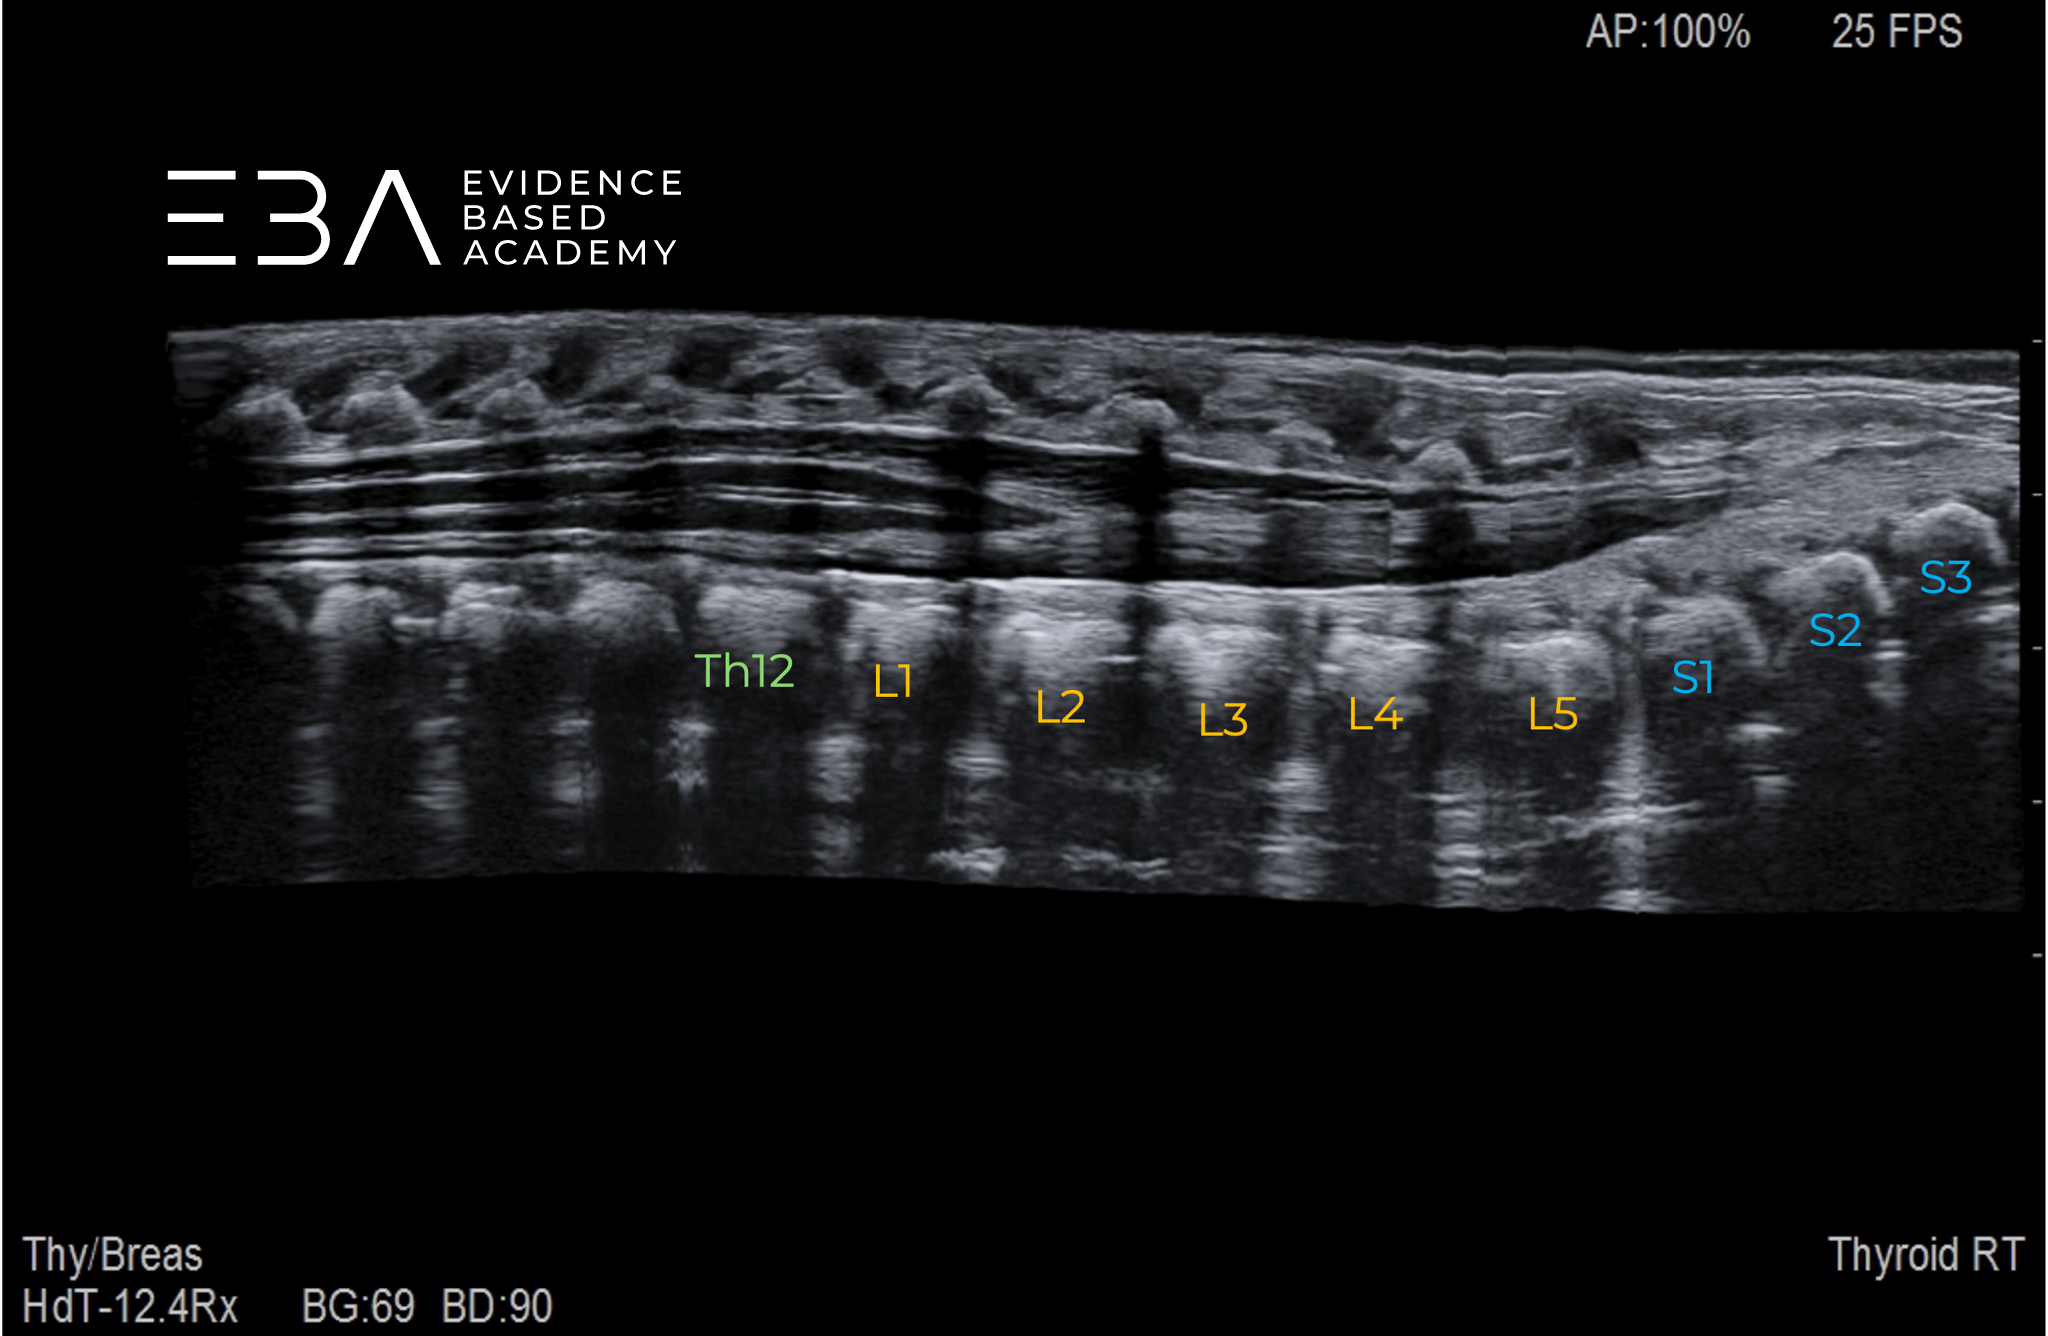

fot. 9

Przekrój podłużny kanału kręgowego – obrazowanie panoramiczne. Numeracja kręgów.

Lokalizacja stożka rdzenia opiera się na dokładnym numerowaniu kręgów.

Najczęstsze podejście do numeracji trzonów kręgów zaczyna się od uwidocznienia połączenia lędźwiowo-krzyżowego po zidentyfikowaniu zaokrąglonej kości guzicznej i kątowo ustawionej kości krzyżowej. Pierwszy trzon kręgu powyżej tego punktu orientacyjnego oznacza L5, kontynuując liczenie w górę dla pozostałych kręgów. Połączenie lędźwiowo-krzyżowe charakteryzuje się zmianą kąta między poziomo zorientowanymi kręgami lędźwiowymi i kręgami krzyżowymi. Pozycję stożka rdzeniowego można też potwierdzić przez liczenie kręgów w dół od żebra 12. lub liczenie dogłowowo od kręgu S5.

USG panoramiczne z rozszerzonym polem widzenia może obrazować długie odcinki kręgosłupa i znacznie ułatwia identyfikację poziomu kręgowego.